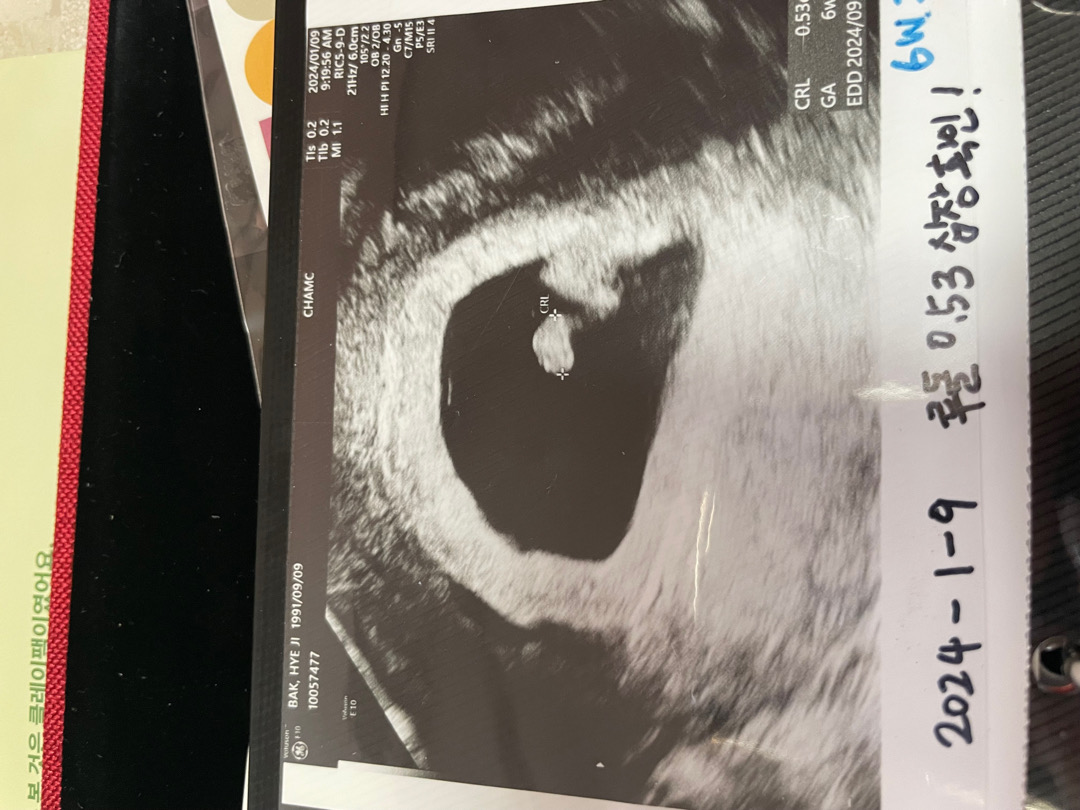

6주 초음파 , 블로그 이웃 하실분 구해보아요!!

https://m.blog.naver.com/hjsdaily/223318992926 6주2일 0.5 cm 작은 아기와 심장 반짝임을 보았어용!! 블로그 서로이웃 구해봅니닷